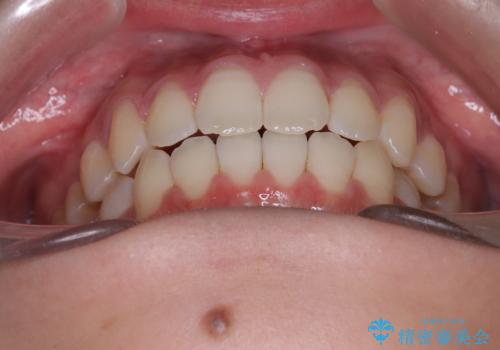

右上小臼歯の捻転を改善|インビザラインと部分ワイヤー矯正のコンビネーション治療

- 右上の小臼歯が大きくねじれており、噛み合わせや見た目に影響を与えている状態でした。診察の結果、インビザライン単独では十分な回転が得られにくいと判断。そのため、基本的な歯列の移動はインビザラインで行いながら、部分的にワイヤー矯正を併用するコンビネーション治療を計画しました。

まず、インビザラインで歯列全体を整えながら、スペースを確保しました。その後、部分ワイヤーを装着し、右上小臼歯の捻転を効率よく改善。ワイヤーの力を活用することで、より確実に歯の向きを整えることができました。治療後は、「しっかり噛めるようになり、見た目も自然になった」と患者様にもご満足いただきました。